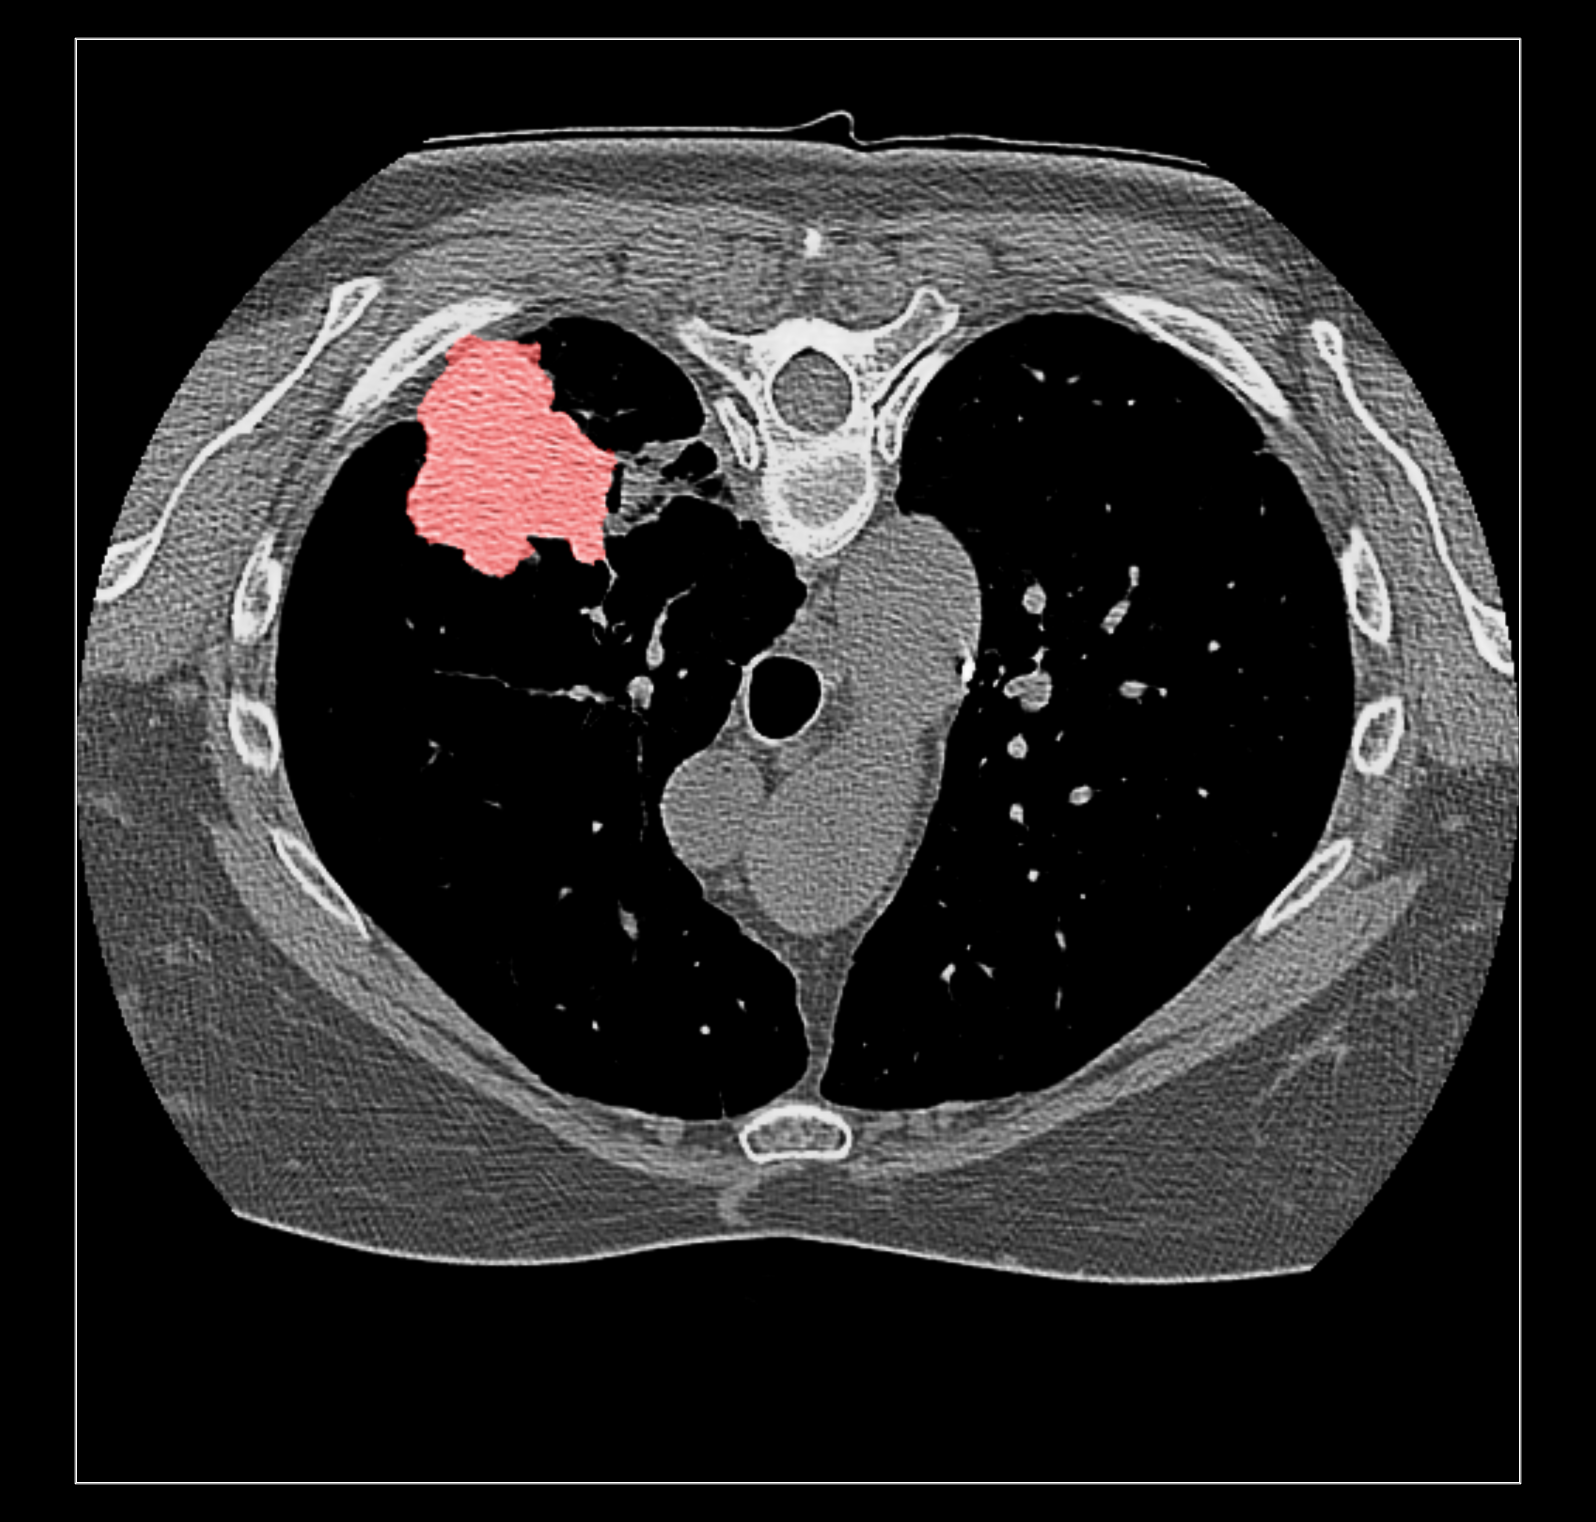

Surface rendering of segmentation channels avoids this problem. But I suspect coloring the image data according to the segmentation is far more useful to researchers looking at medical imaging because unlike a surface it allows you to see the intensities in the segmented region. For instance that helps you judge if the segmentation is correct. Sometimes a surface is best, for instance if you just want to see the size of a segmented tumor or compare the size a month ago to now using transparent surfaces can do that. I guess my overall assessment is that good quality medical imaging visualization needs the fancier blending. Because medical imaging is significantly different from electron and light microscopy there will be different needs that may be hard to implement like this blending problem. The priority of such time consuming improvements needs to be guided by medical imaging users.

Surface rendering of a segmentation with image rendering of a CT scan can look ok, and only the outline of the surface can be shown using volume command "capFaces false". Showing both segmentation and CT as image also works fine if the brightness curve is not narrow. I've attached images for all 3 styles made with

The capped surface flickers badly when rotating because the surface cap is at exactly the same depth as the image plane so a rendering depth fight ensues.

The surface outline is so thin on a retina display it is hard to see. Currently we don't support thicker lines because thick line support was dropped in modern OpenGL.

The surface style with plane CT image display adjusts when the plane is moved with the slider since the CT and segmentations are grouped as multichannel volume data.